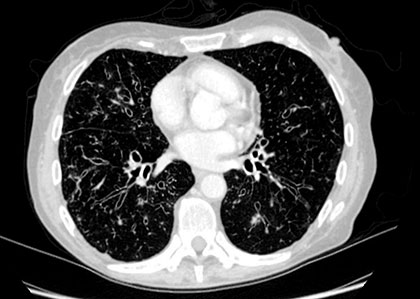

Saiba maisMetástases Pulmonares

A Metástase Pulmonar é um quadro grave e que deve receber tratamento desde o início para garantir a recuperação do paciente